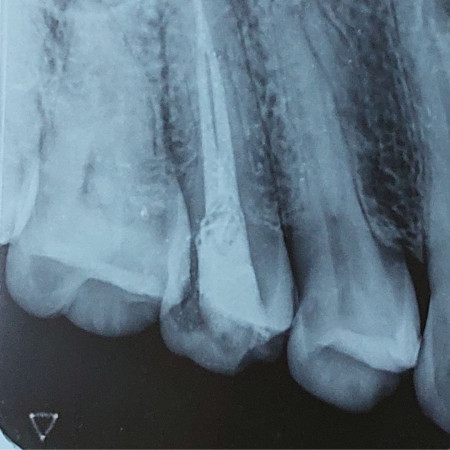

One Visit Root Canal Treatment

When a tooth is infected or the pulp is exposed due to dental trauma, it can be saved by doing a root canal treatment, commonly known as a Nerve filling. 95% of our root canal treatments are completed in one visit, which in turn saves your time and reduces radiation exposure too. We take pride in delivering root canal treatments with minimum post-operative pain and only a very few patients require post-operative use of Antibiotics.

Advanced Complex Root Canal Treatments And Re-treatments

Not all root canal treatments are straightforward. The shape and degree of formation of the root of some teeth require expert intervention. We are proud to house some of the best-trained specialists at Danthaja to handle such cases. Furthermore, failed root canal treated cases done elsewhere, which need re-treatment will also be handled by our specialists.